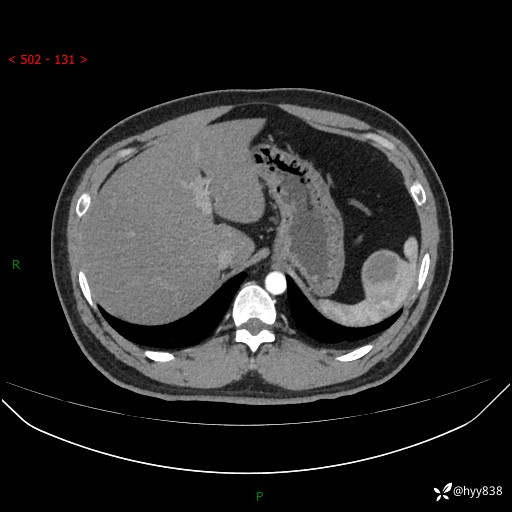

【患者信息】:31岁/男

【主诉】:超声发现脾脏肿物,为进一步诊治来我院,门诊以“脾脏占位”收入院

【检查】:上腹部CT平扫+增强